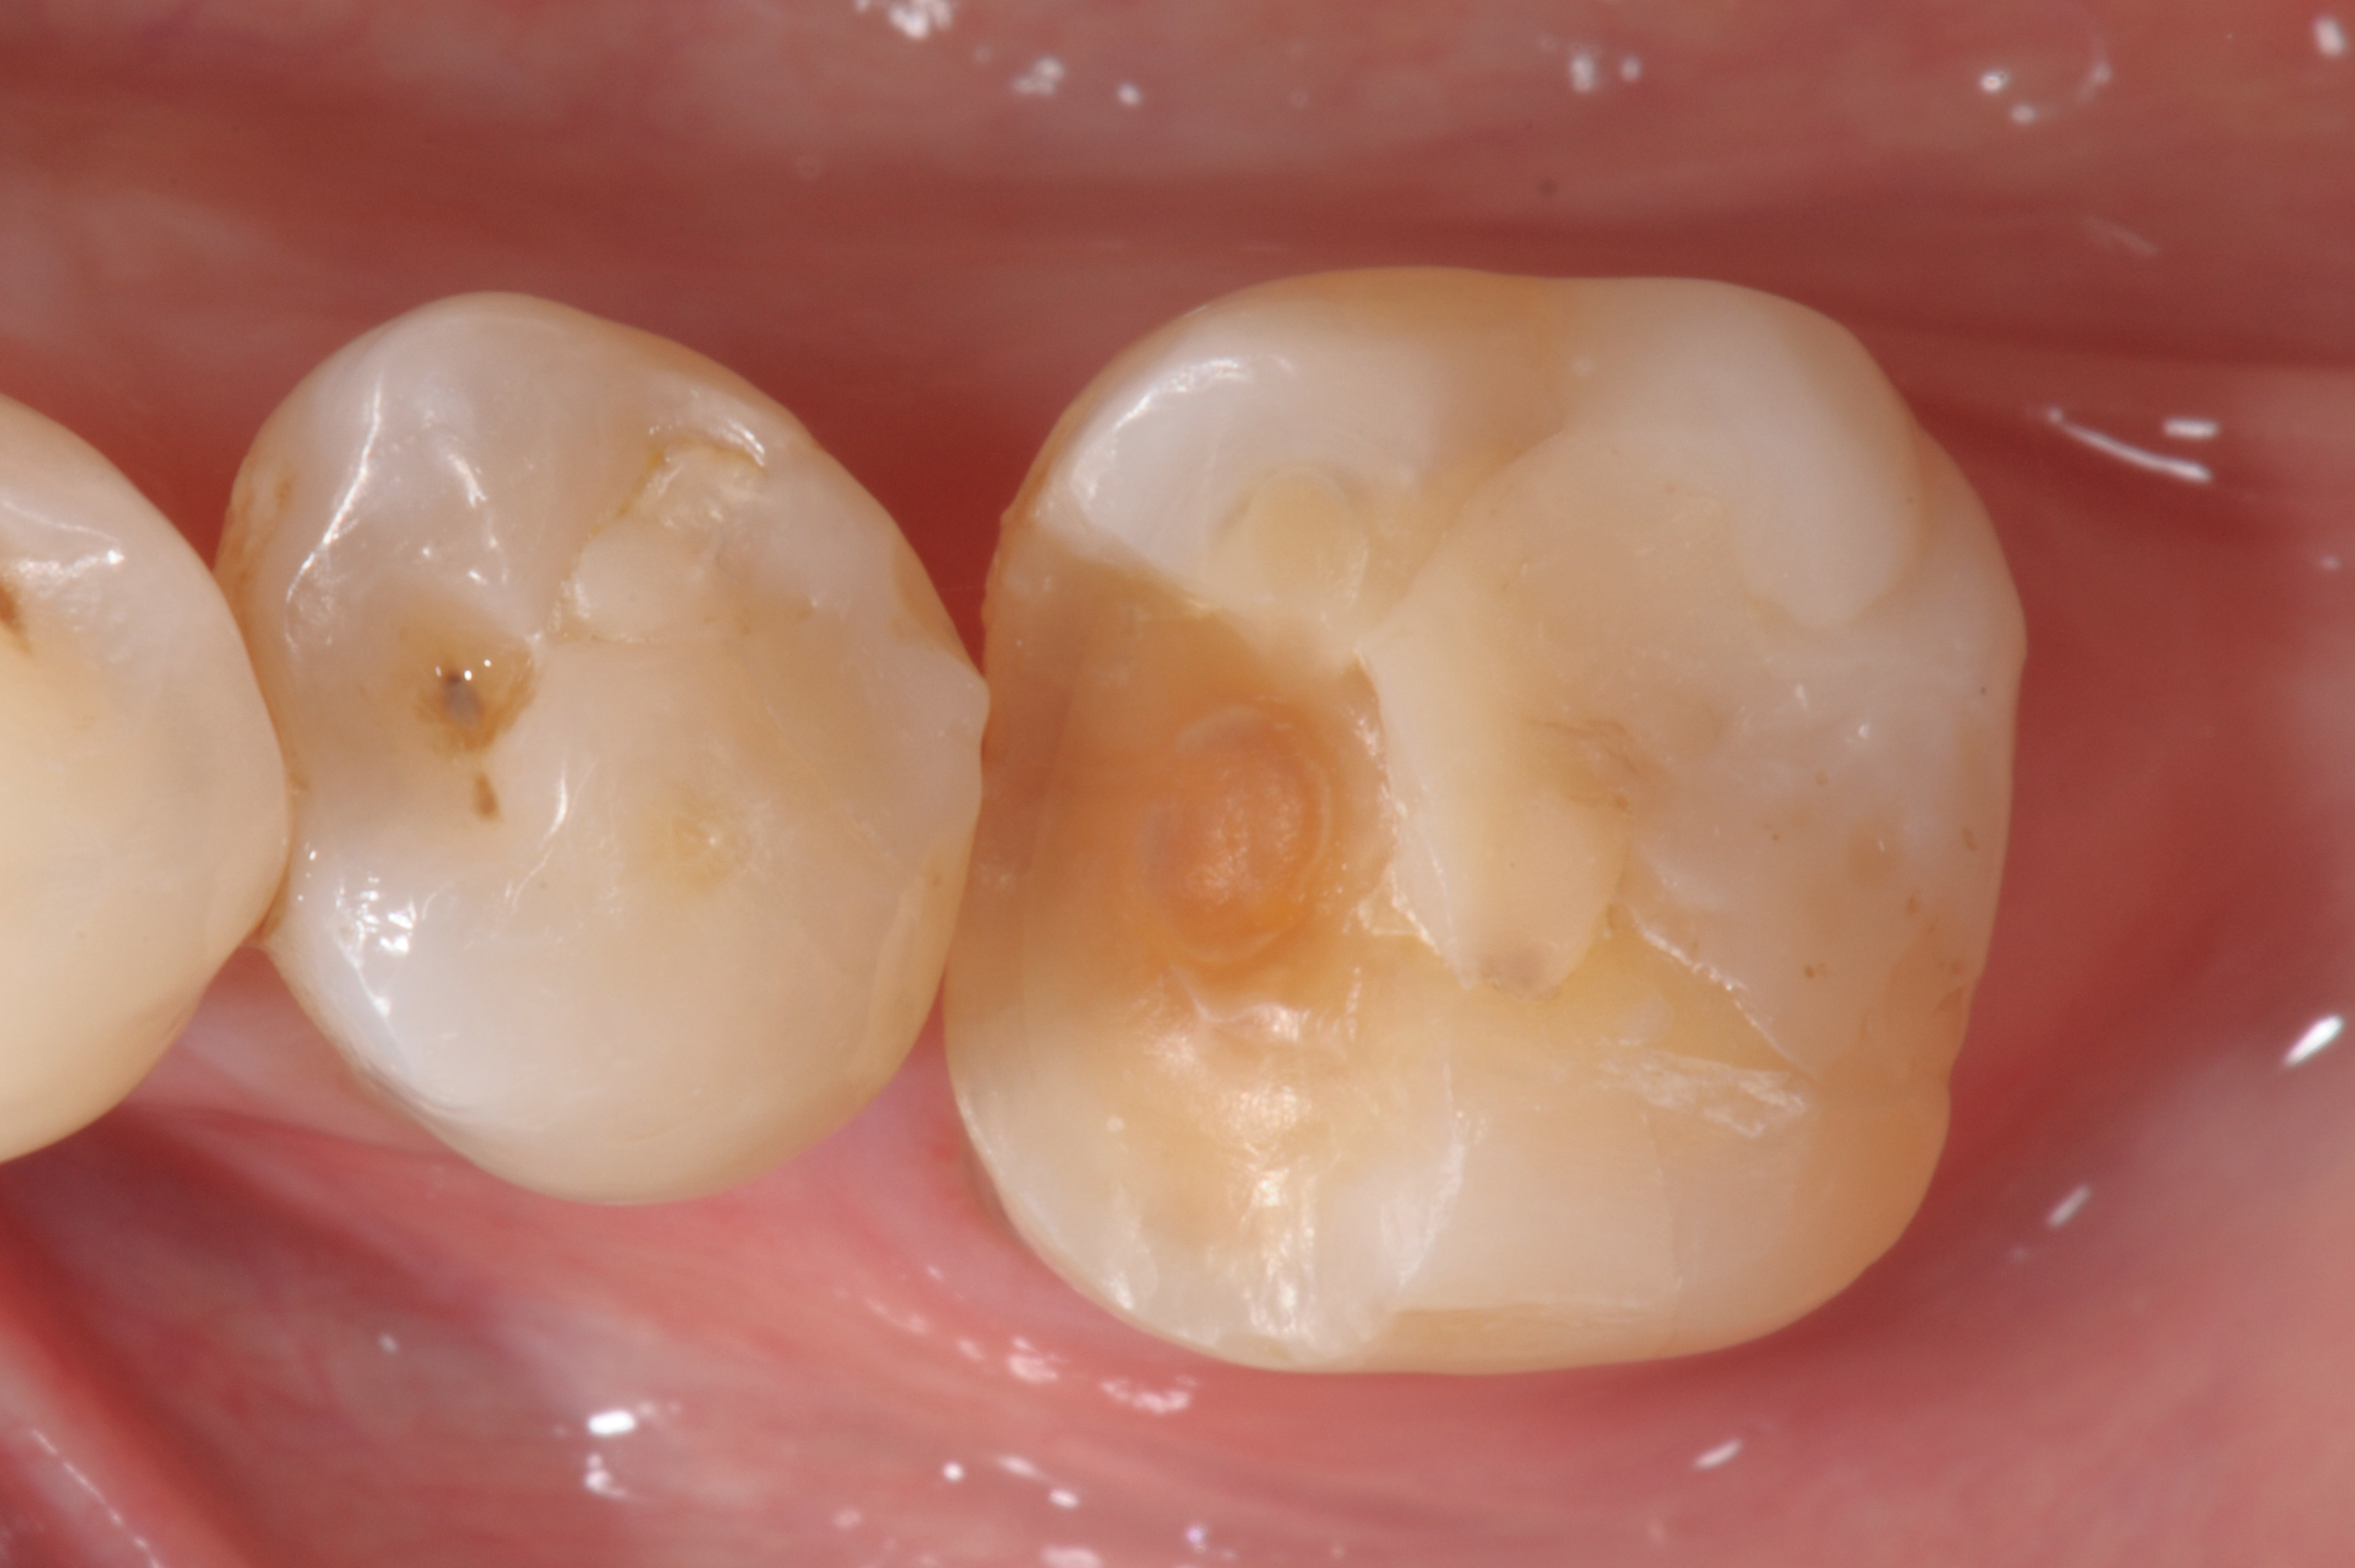

Fig 4. Postoperative view.

Figure 4

When following a protocol of cementation using an adhesive system, constant rubber dam isolation and careful hand finishing are necessary to provide predictable clinical results (Figure 1 through Figure 4).2